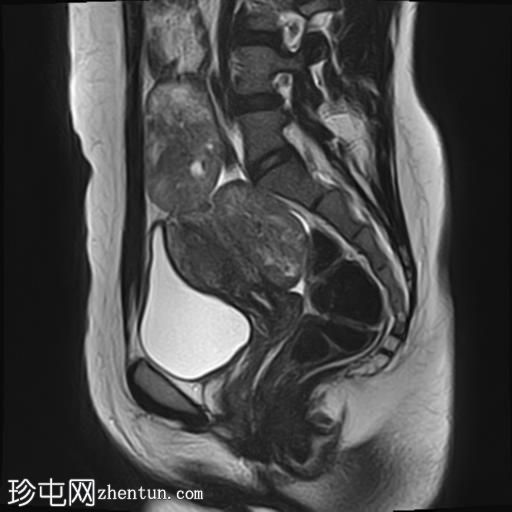

轴位

T2加权像

其中一个位于子宫上方,T2加权像呈中等信号,中心区域呈高信号,增强T1脂肪抑制像未见强化。右侧卵巢增大,增厚的血管蒂扭曲,未见强化,轴位和矢状位T2加权像均显示清晰。

另一个位于子宫后窝,T2加权像呈中等信号,增强扫描显示明显强化。

轻度腹腔积液